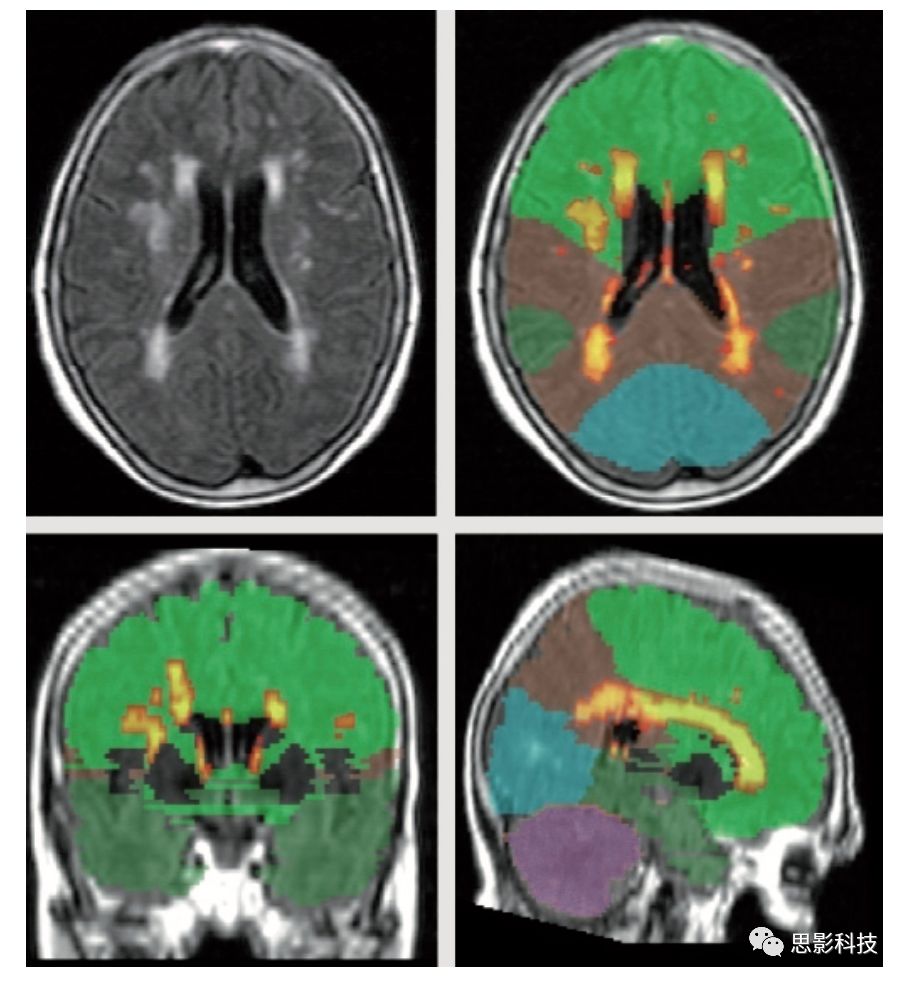

老年人腦白質高信號嚴重程度的最優(yōu)表征一直備受爭議。部分研究人員認為室周WMH在臨床中不如深部WMH重要。部分研究人員強調了WMH區(qū)域及分布的重要性。這些特征反映在許多視覺評分量表中,例如Scheltens量表,評估WMH的嚴重程度和分布的常用方法。本實驗室開發(fā)了一種局部WMH嚴重程度分析的定量方法。簡單地說,通過考慮每個被試FLAIR圖像的體素強度分布,將高斯曲線擬合到每個大腦半球,并推導出每個半球的均值和標準差,WMH種子點被定義為高于或等于平均值2.5倍標準差。左邊和右邊的種子點被合并,然后每個種子點被傳遞到一個基于平均強度的局部生長算法。該算法使用種子點體素強度作為其起始平均值,并應用10點連接方案(x-y平面,1個在z平面上,1個在z軸下),搜索并標記落在種子均值5%以內的體素。相鄰體素信號下降低于5%被添加到圖像中,并創(chuàng)建一個新的平均值。該過程不斷迭代,直到所有種子都包含在最終的WMH圖像中。標記為WMH的體素數(shù)量乘以體素維度得到WMH總體積。通過對每張圖像進行空間標準化至解剖圖譜,可得到主要解剖腦葉、基底節(jié)區(qū)及小腦WMH體積。圖3展示了FLAIR圖像三個正交視圖,其中標記WMH并進行局部分割。此外,通過對側腦室分割(圖4),可以計算每個體素至側腦室壁的三維距離。因此,該定量處理方法可以用來導出WMH的總體積、局部WMH體積,以及室周和深部WMH體積。

3. 個被試的局部WMH。

左上角:T2 FLAIR原始圖像。右上和下排:WMH標記,顏色越亮表示體素信號強度越高。

顏色對應大腦各葉(綠色:額葉,棕色:頂葉,深綠色:顳葉,藍色:枕葉,淡紫色:小腦)

4. 高分辨率T1加權解剖掃描的軸向和矢狀正交圖像,疊加腦室分割(紅色)通過分割側腦室,能夠計算出每個WMH體素與室壁的距離。